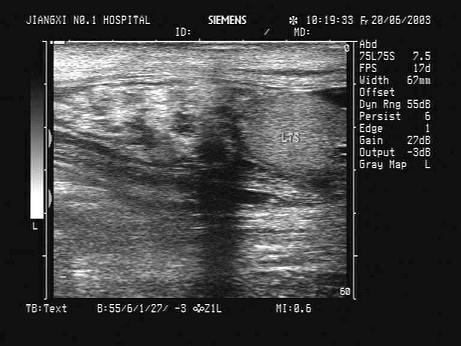

问题 某患者阴囊增大,自诉用力时阴囊可增大,平卧缩小,无外伤史。B超检查超声声像图如下,最可能的诊断为?(?)

选项 A.鞘膜积液 B.附睾炎性包块 C.斜疝 D.附睾结核 E.股疝

答案 C